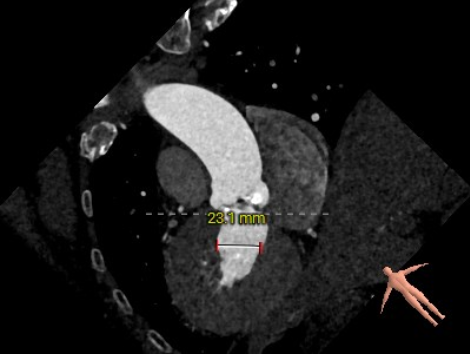

主动脉根部评估:

短轴

长轴

三叶式主动脉瓣;瓣环周长23mm,平均周长径72.1mm;左冠脉开口高度大于瓣叶长度;综合考虑冠脉风险低;LVOT周长径22.6mm;升主动脉直径32.1mm。

左冠高度12.1mm,右冠高度14.1mm;右冠脉开口高度大于瓣叶长度;SOV瓦式窦:平均周长径31.3mm;术中球囊预扩须密切注意冠脉灌注;STJ周长径26.5mm。